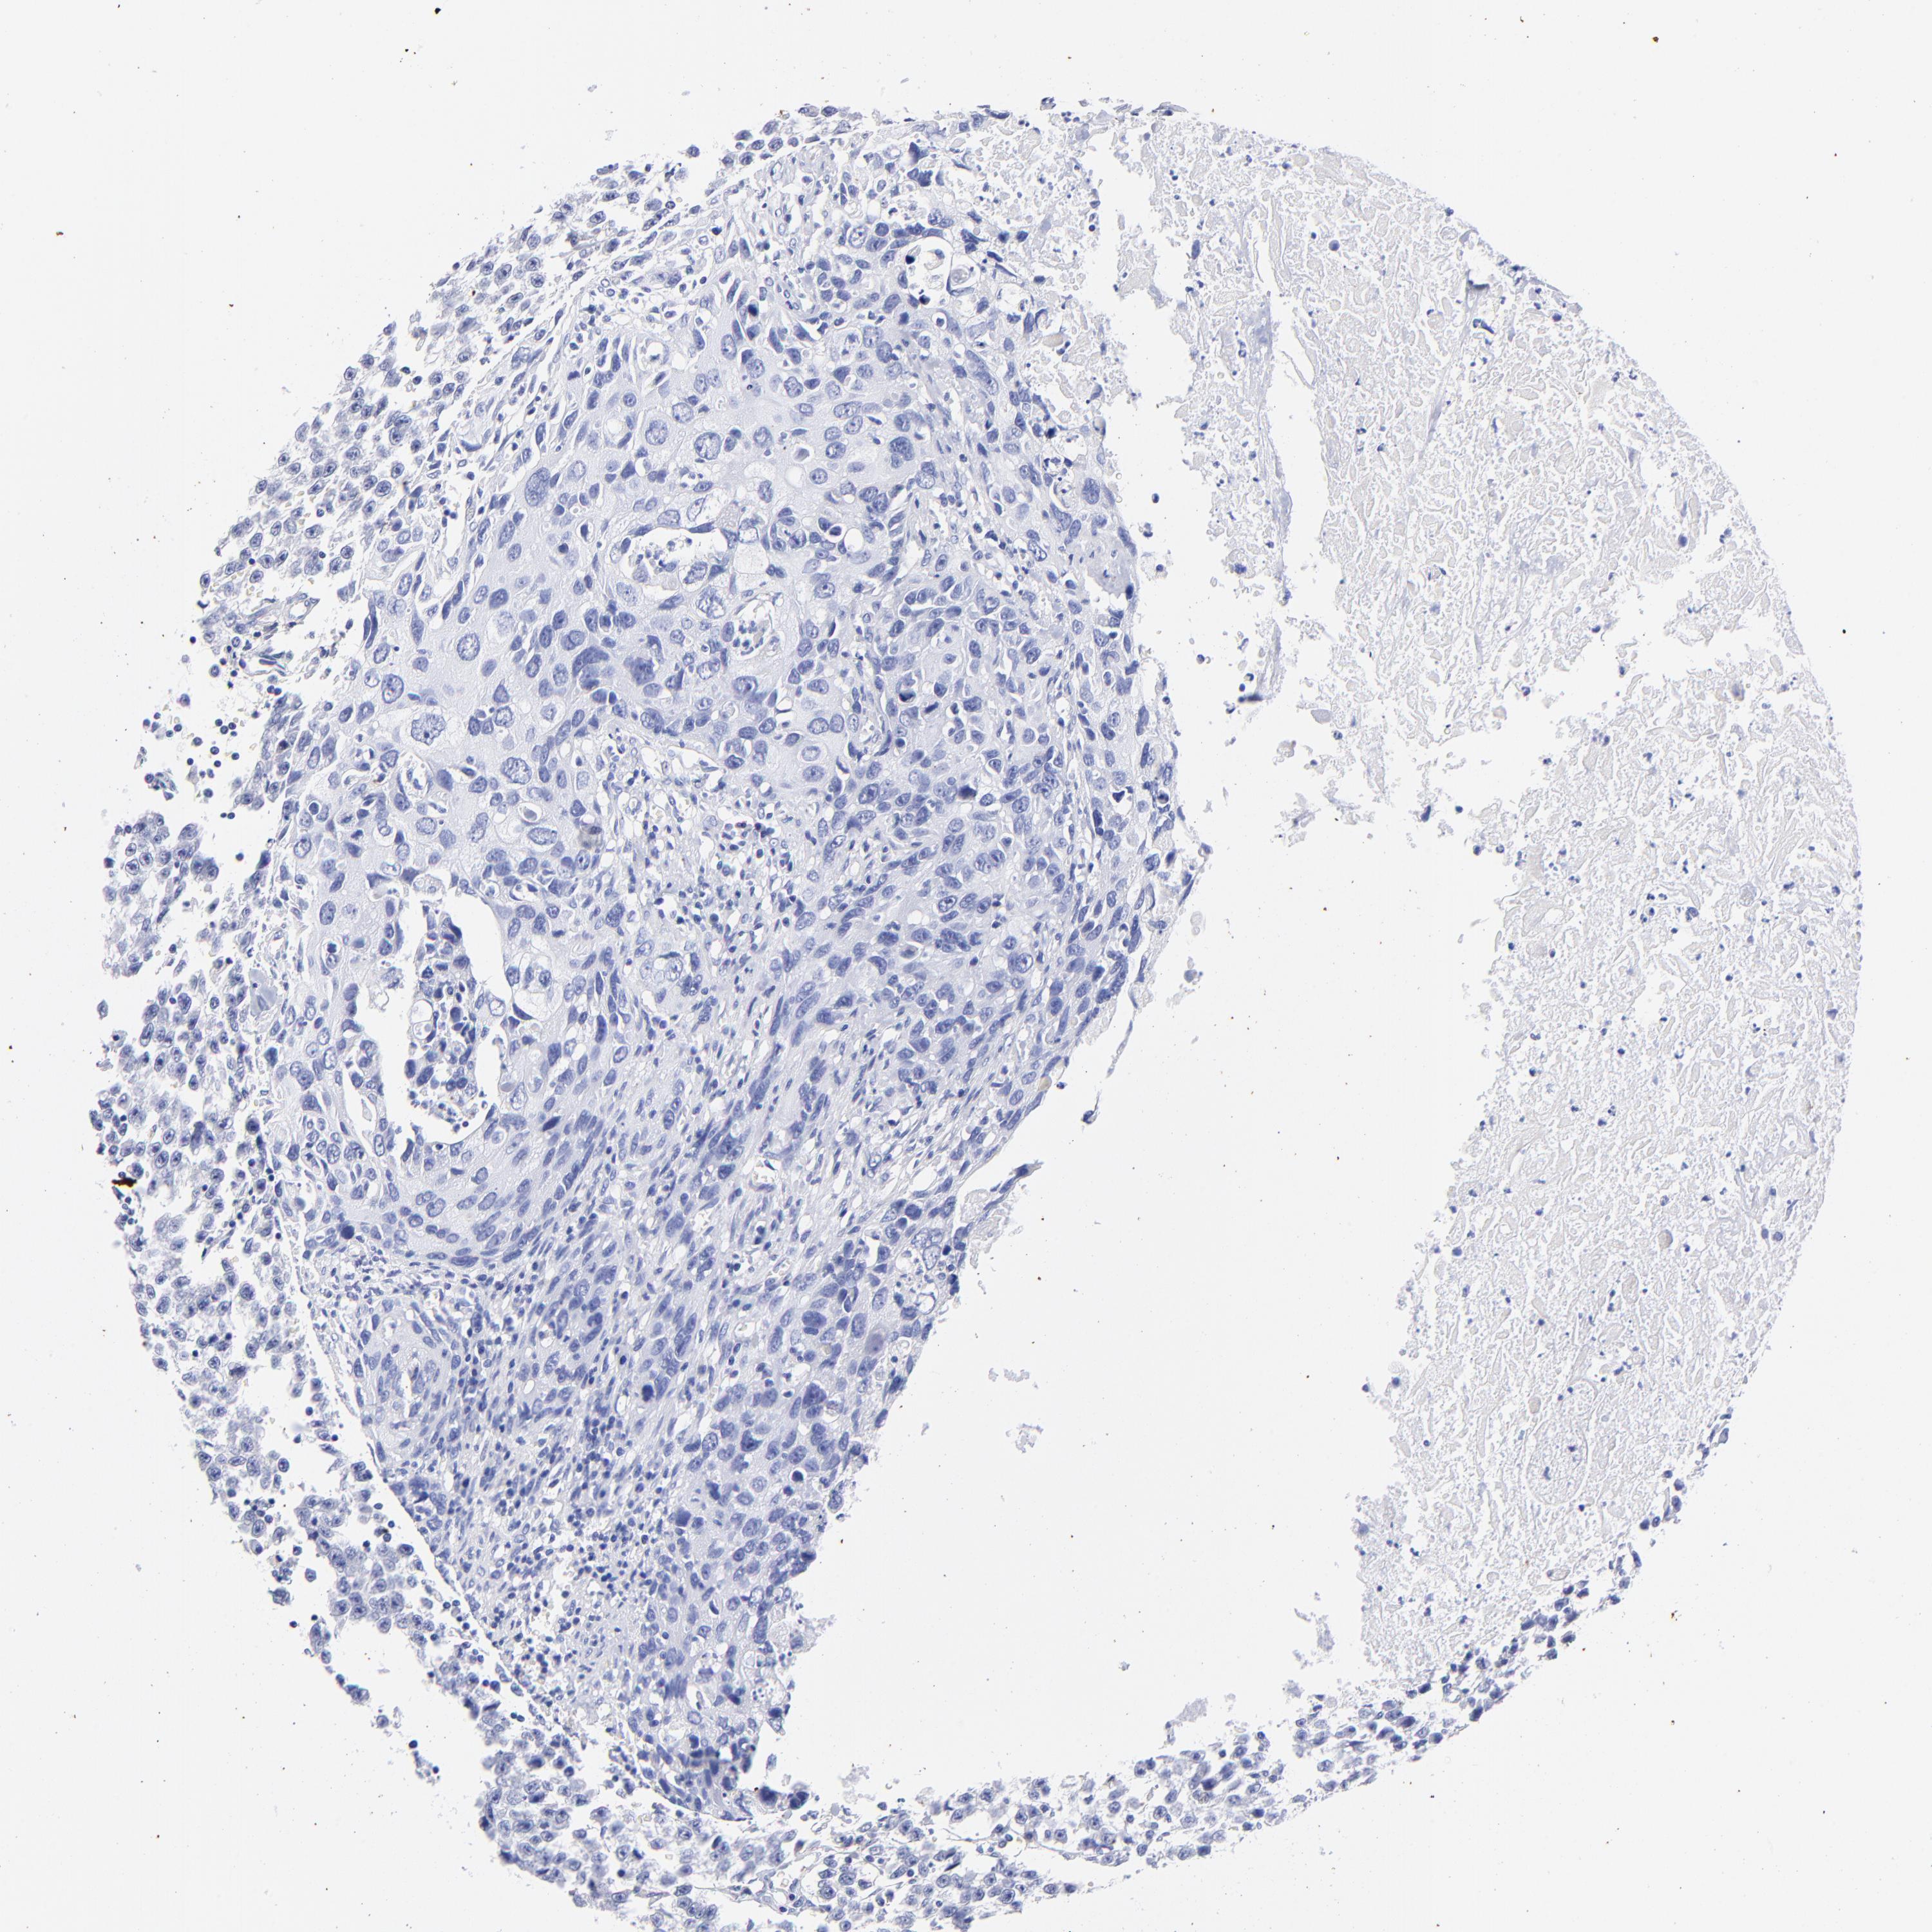

UROTHELIAL CANCER - Protein expressioni

A mouse-over function shows sample information and annotation data. Click on an image to view it in a full screen mode. Samples can be filtered based on level of antibody staining by selecting one or several of the following categories: high, medium, low and not detected. The assay and annotation is described here.

Note that samples used for immunohistochemistry by the Human Protein Atlas do not correspond to samples in the TCGA dataset.

Antibody stainingi

Antibody staining in the annotated cell types in the current human tissue is reported as not detected, low, medium, or high, based on conventional immunohistochemistry profiling in selected tissues. This score is based on the combination of the staining intensity and fraction of stained cells.

Each image is clickable and will lead to virtual microscopy that enables deeper exploration of all samples and also displays staining intensity scores, fraction scores and subcellular localization as well as patient and tissue information for each sample.

Antibody HPA003074

Staining

High

Medium

Low

Not detected

Intensity

Strong

Moderate

Weak

Negative

Quantity

>75%

75%-25%

<25%

None

Location

Nuclear

Cytoplasmic/membranous

Cytoplasmic/membranous,nuclear

Urothelial carcinoma, Low grade